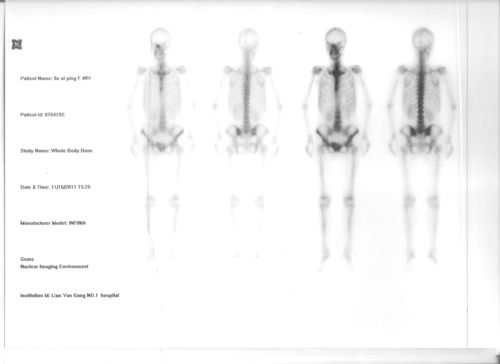

人体骨骼放射扫描图像

求影像核医学专业的医生帮看一下我母亲的spect(全身骨扫描)结果,图片

骨扫描图片

正常骨扫描图片

全身骨扫描图片

骨扫描显示骨转移图片

肺癌骨转移骨扫描图片

骨扫描骨转移报告图

骨扫描正常报告单图片